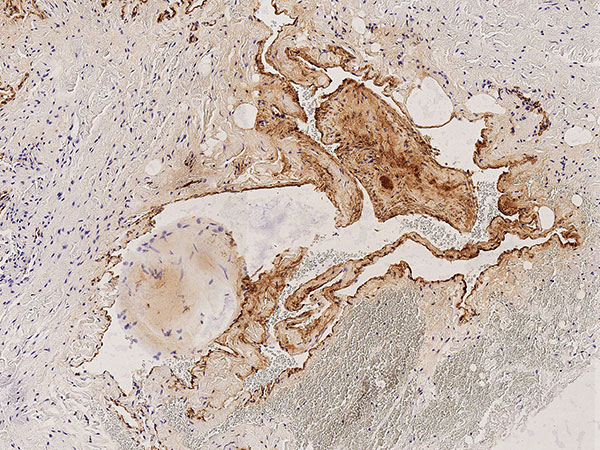

Histopathologie, CD31-Färbung, 110-fache Vergrößerung: Die starke Anfärbung (dunkelbraun gefärbte Endothelzellen) mit dem gefäßendothel-spezifischen Marker CD-31 der gesamten Begrenzung der irregulären, gefäßartigen dysplastischen Hohlraumstruktur weisst klar auf eine Gefäßmalformation hin. Unter dem Gefäßendothel ist nur eine sehr dünne Gefäßwandung nachweisbar.